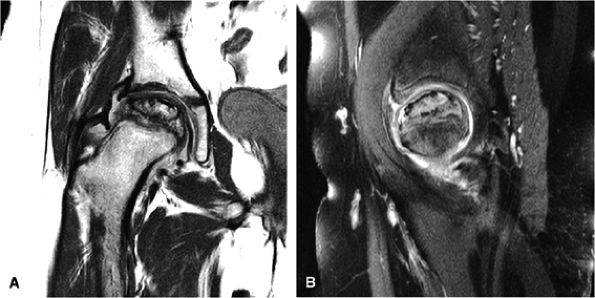

FIGURE 3.48 ● (A) Articular surfaces of the hip joint comprise the acetabulum of the hip bone and the head of the femur. (B) A sagittal MR arthrogram of the hip demonstrating capsular distention and the articular relationship of the femoral head (H) to the anterior (A) and posterior (P) aspects of the acetabulum and ilium (I). Fat-suppressed T2-weighted fast spin-echo.